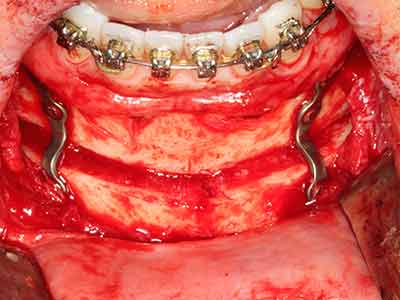

When surgical procedures are performed on bone in the immediate vicinity of sensitive structures such as blood vessels or nerves, rotary instruments pose a significant risk of iatrogenic injury. Piezoelectric devices can be helpful for preparation of bone covers and removal of hard tissue close to nerves, particularly for exposure of nerves after iatrogenic injury but also during nerve lateralization for resective and reconstructive procedures or implant placement (Fig. 17-20). Light contact between the piezotip and the nerve does not generally result in damage but proceeding incautiously with saw-like motions or attachments where a residual bone substrate remains may cause temporary or even permanent nerve damage. However, the risk of damage is considered to be substantially lower than when using saws or milling instruments (Pereira, Gealh et al. 2014).